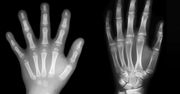

To nie mózg decyduje o tym, której ręki używamy